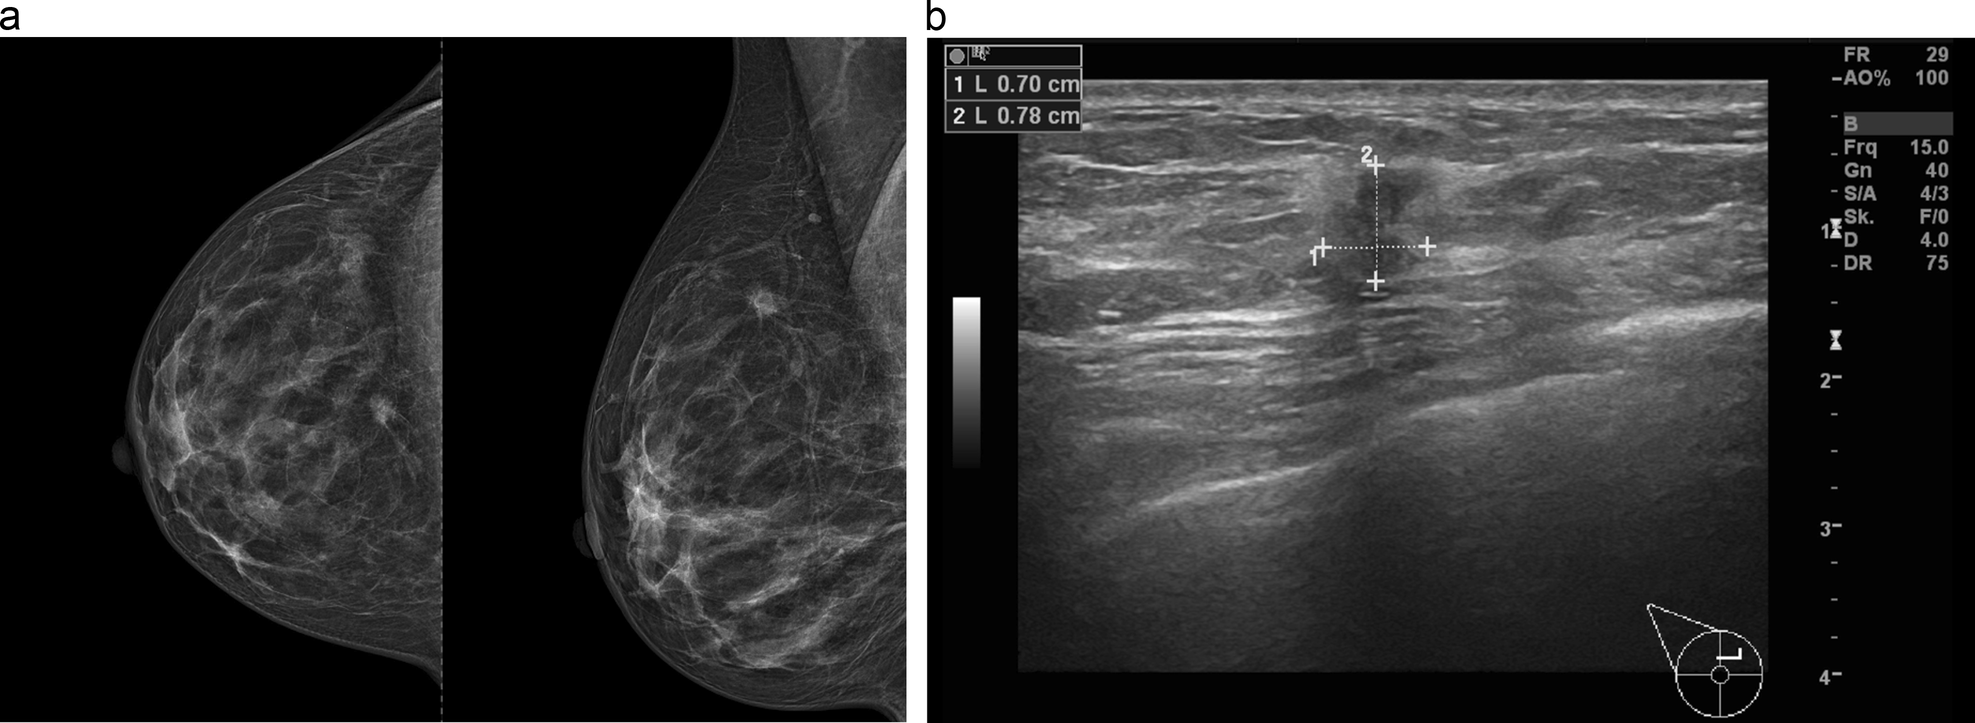

Fig. 3

55-year-old woman without significant family/personal risk factors for breast cancer undergoing routine breast cancer screening examination. In the right mammogram (a cranio-caudal and mediolateral oblique projections) scattered areas of fibroglandular density can be observed. A suspicious irregular shaped and spiculated mass can be seen at 12 o’clock. At ultrasound a corresponding irregular shaped, spiculated and hypoechoic mass up to 0.8 cm can be seen (b). Ultrasound-guided biopsy was performed and the mass histologically corresponded to a NST moderately differentiated invasive ductal carcinoma